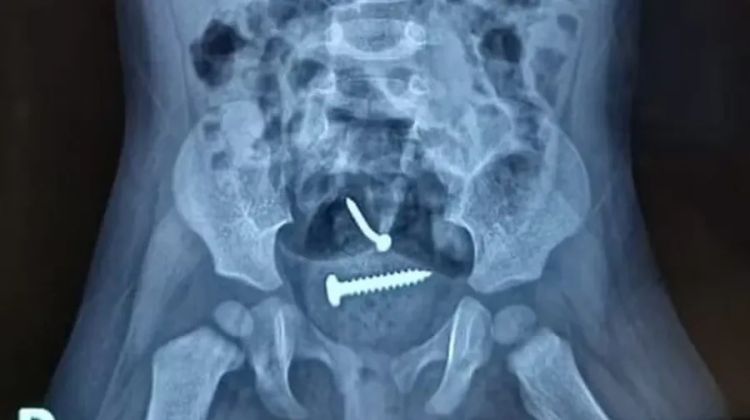

O laudo médico da bebê de 1 ano, que estava com um prego e parafuso dentro do corpo, revela que não houve violência sexual. O suspeito de ter agredido mãe e filha prestou depoimento na delegacia da cidade de Pedro II e negou ter abusado da bebê.

A sua companheira também negou, que o pai tenha cometido algo contra a criança. O laudo também mostrou que a criança engoliu os objetos e que os mesmos foram expelidos de forma natural, não precisando de intervenção cirúrgica.